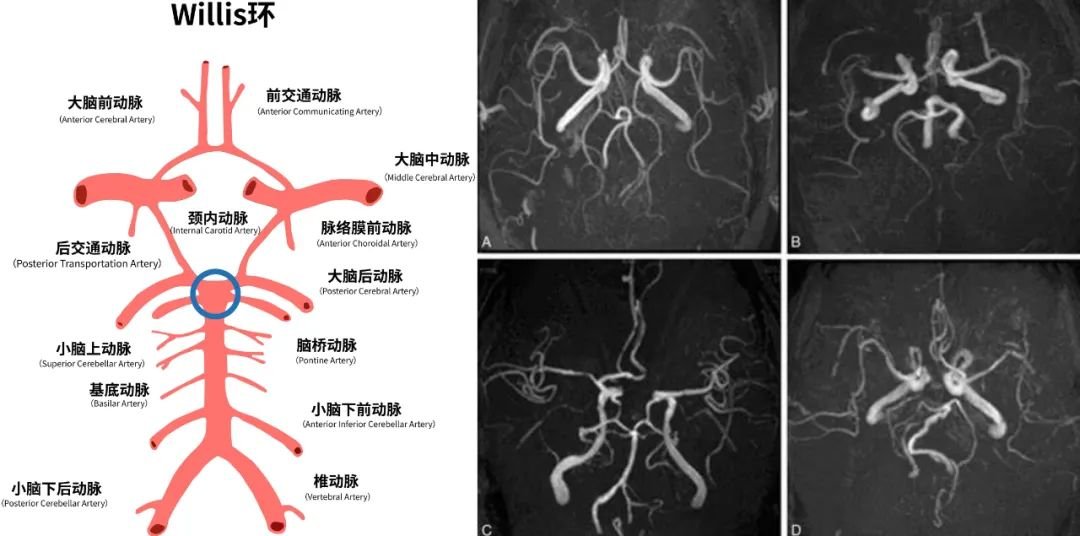

雖然有一些顱咽管瘤鏡下一看確實(shí)難度很大,黏連嚴(yán)重,不止是和它起源的部位,甚至跟周圍的血管,因?yàn)樗麄€(gè)顱咽管瘤起源的地方,還有一個(gè)叫做Willis環(huán)的結(jié)構(gòu),它就像閃亮紅星一樣,散散發(fā)光,特別耀眼。

它又被稱為大腦動(dòng)脈環(huán),是指供應(yīng)腦組織的動(dòng)脈在腦底形成的環(huán)狀結(jié)構(gòu)。它是顱內(nèi)較重要的側(cè)支循環(huán)途徑,將雙側(cè)大腦半球和前、后循環(huán)聯(lián)系起來(lái)。